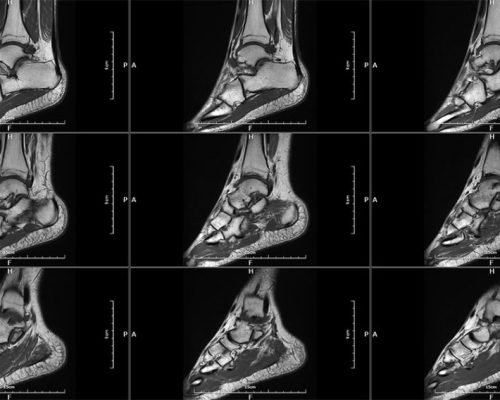

MICA represents the pinnacle of innovation in 1.5T whole-body MRI systems, delivering image quality rivaling 3T systems through its unique High-Temperature Superconducting (HTS) RF coil technology.

MICA is the result of our commitment to develop the world’s highest performing 1.5T whole body MRI system with integrated superconducting RF coil. The superb image quality targeting 3T system performance level is made possible with the unique High-Temperature Superconducing (HTS) RF coils patented by Time Medical Systems.

High-performance gradient system enables faster scanning and sharper images, ideal for advanced neurological and musculoskeletal applications.